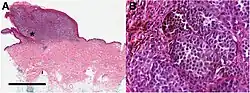

Melanoma in skin biopsy with H&E stain – this case may represent superficial spreading melanoma. -

Biopsy

Following a visual examination and a dermatoscopic exam, or other specialized tests such as confocal microscopy, a skin biopsy is done for lesions suspicious of being melanoma. A skin biopsy is required for definitive diagnosis of melanoma and staging the cancer.[11] Elliptical excisional biopsies may remove the tumor, followed by histological analysis and Breslow scoring. Incisional biopsies such as punch biopsies are usually contraindicated in suspected melanomas, because of the possibility of sampling error or local implantation causing misestimation of tumour thickness.[81][82][83] However, fears that such biopsies may increase the risk of metastatic disease seem unfounded.[84][85]